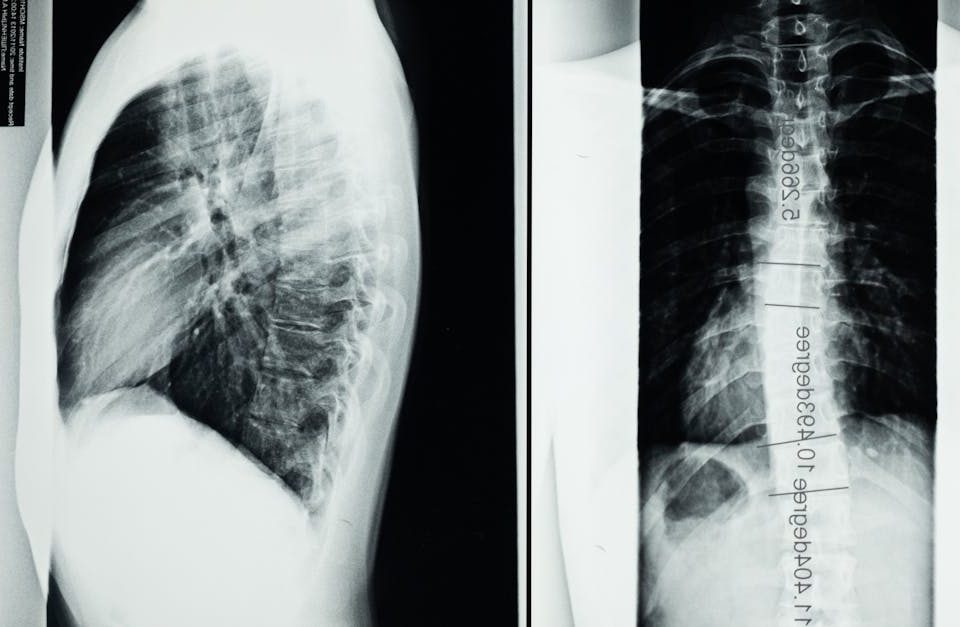

Dans cette catégorie, découvrez une approche innovante et non invasive pour soulager les douleurs liées à l’arthrose facettaire, une condition dégénérative affectant les articulations des facettes vertébrales. La décompression neurovertébrale agit en réduisant la pression exercée sur les facettes et les structures environnantes, aidant à diminuer l’inflammation et à améliorer la mobilité. Nos articles expliquent les mécanismes et les avantages de cette thérapie, notamment la réduction de la douleur, le ralentissement de la dégénérescence et l’amélioration de la qualité de vie. Basée sur des données scientifiques, cette approche constitue une solution efficace et sécuritaire, intégrée dans une stratégie globale de gestion des douleurs vertébrales chroniques.

Arthrose facettaire

EN BREF La décompression neurovertébrale est une approche thérapeutique innovante destinée à améliorer la posture des patients souffrant de déséquilibres musculo-squelettiques complexes. En appliquant une traction […]